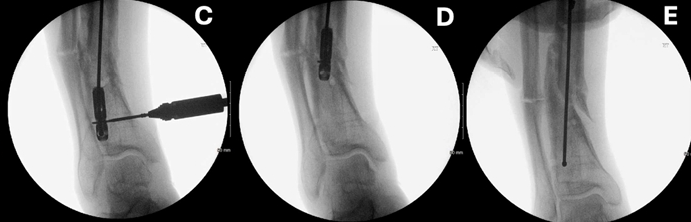

手术案例2:一例87岁男性患者长头髓股骨髓内钉的取出过程(图1A)

A. 将远端锁定螺钉部分旋出。

B、C. 将橄榄头导丝送至髓内钉末端,并在原锁定螺钉孔内置入微型螺钉。

D. 小心回抽导丝,使其与微型螺钉嵌合,同时不退出螺丝刀。

E. 轻拉导丝,将髓内钉取出。

F. 取出后的断裂髓内钉,可见导丝及位于螺钉孔内的微型螺钉。